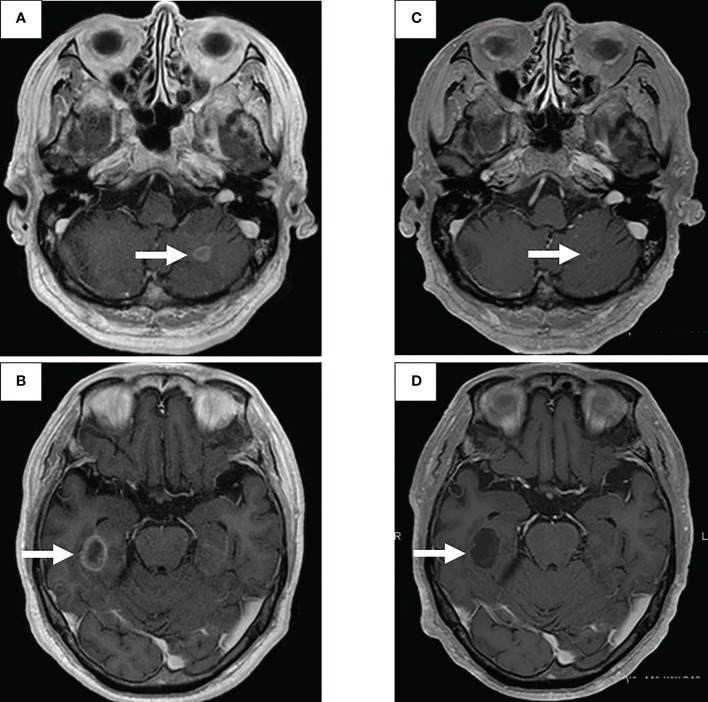

圖2:使用二線治療塞爾帕替尼的腦轉(zhuǎn)移療效

通過支氣管鏡對原發(fā)病灶進行再活檢,細胞學(xué)評估顯示V級腺癌,組織學(xué)評估證實了這一結(jié)果。腫瘤正確用藥850基因檢測確認(rèn)患者為RET融合基因陽性,隨后于第二天給予240mg塞爾帕替尼。第13天的CT顯示與基線影像相比(圖1H),所有轉(zhuǎn)移病灶,包括腦轉(zhuǎn)移(圖2C、D),均有良好的全身反應(yīng)。由于2級肝酶升高,繼續(xù)給予劑量減少的塞爾帕替尼(每天160mg)。使用高敏感度的下一代測序(NGS)面板系統(tǒng):肺癌緊湊面板,并使用細胞學(xué)刷液進行RNA檢測,證實了融合基因KIF5B外顯子15;RET外顯子12(K15RET12)。腫瘤正確藥基因解碼基因檢測還能夠從7年前的胸腔積液細胞塊的福爾馬林固定石蠟包埋(FFPE)標(biāo)本中進一步確認(rèn)RET(圖3A、B),這些標(biāo)本在惡性細胞的形態(tài)學(xué)上與再活檢樣本相似,具有大核仁(圖3C、D)。從初始細胞塊樣本中收集到的RNA(1256ng)具有RNA整合數(shù)(RIN)值為4.8。單重PCR和NGS檢測均檢測到了K15RET12融合峰(圖3)。